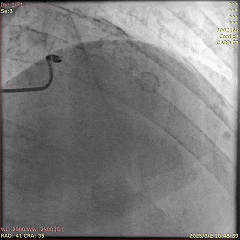

基于动态心电图变化情况进行综合分析,确定LAD为罪犯病变,成功植入药物洗脱支架进行治疗,并对第一对角支进行了血管成形术。术后患者胸痛缓解,转入CCU。

首次PCI的冠脉造影(植入支架后)